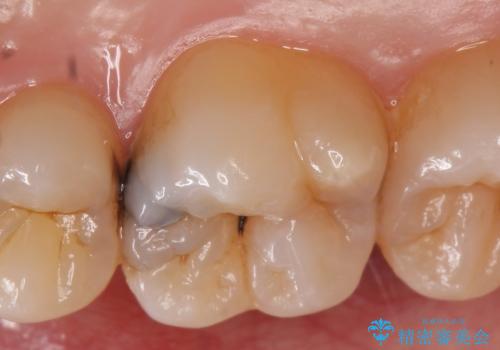

- 右上の奥歯で冷たいのもがしみるといらっしゃった方の症例です。

虫歯を除去後、セラミックインレーによる修復を行いました。

当院のセラミックインレーはemaxという強度と審美性に優れた材料を使用しています。

またプレス方式でインレーを製作しているため、削り出しで製作するCADCAMより優れた適合性も持ち合わせており、虫歯が再発しにくい修復物です。